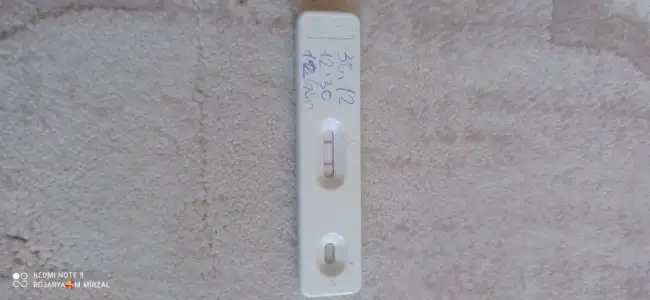

Cnm nasil yaptin anlatsan erkek bebek icin esin fala kan verdimi cin takvimi tuttumjZor oluyormuş evet bu ay takip yapıyorum sadece önümüzdeki ay nasipse hem doktor kontrolü hemde testle deneme yapacağım inşaallah